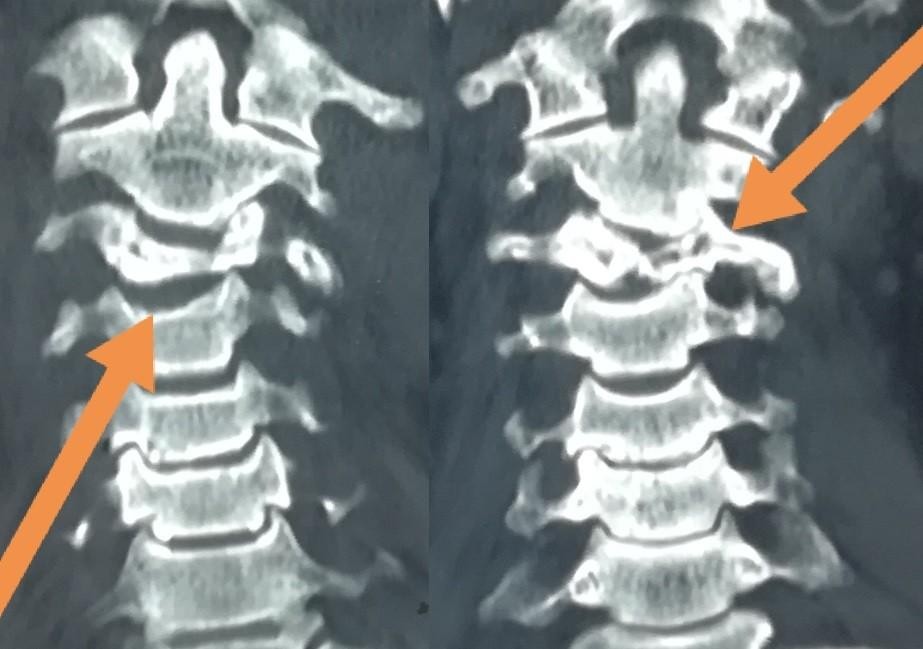

تثبيت امامي لكسر وتاكل بجسم الفقرة الثالثة العنقية

anterior fixation of a fracture and wear of the body of the third cervical vertebra

A successful anterior fixation surgery was performed to treat fracture and erosion in the vertebral body of cervical vertebrae. This specialized procedure aims to restore cervical spine stability and address vertebral damage resulting from injury or inflammation.